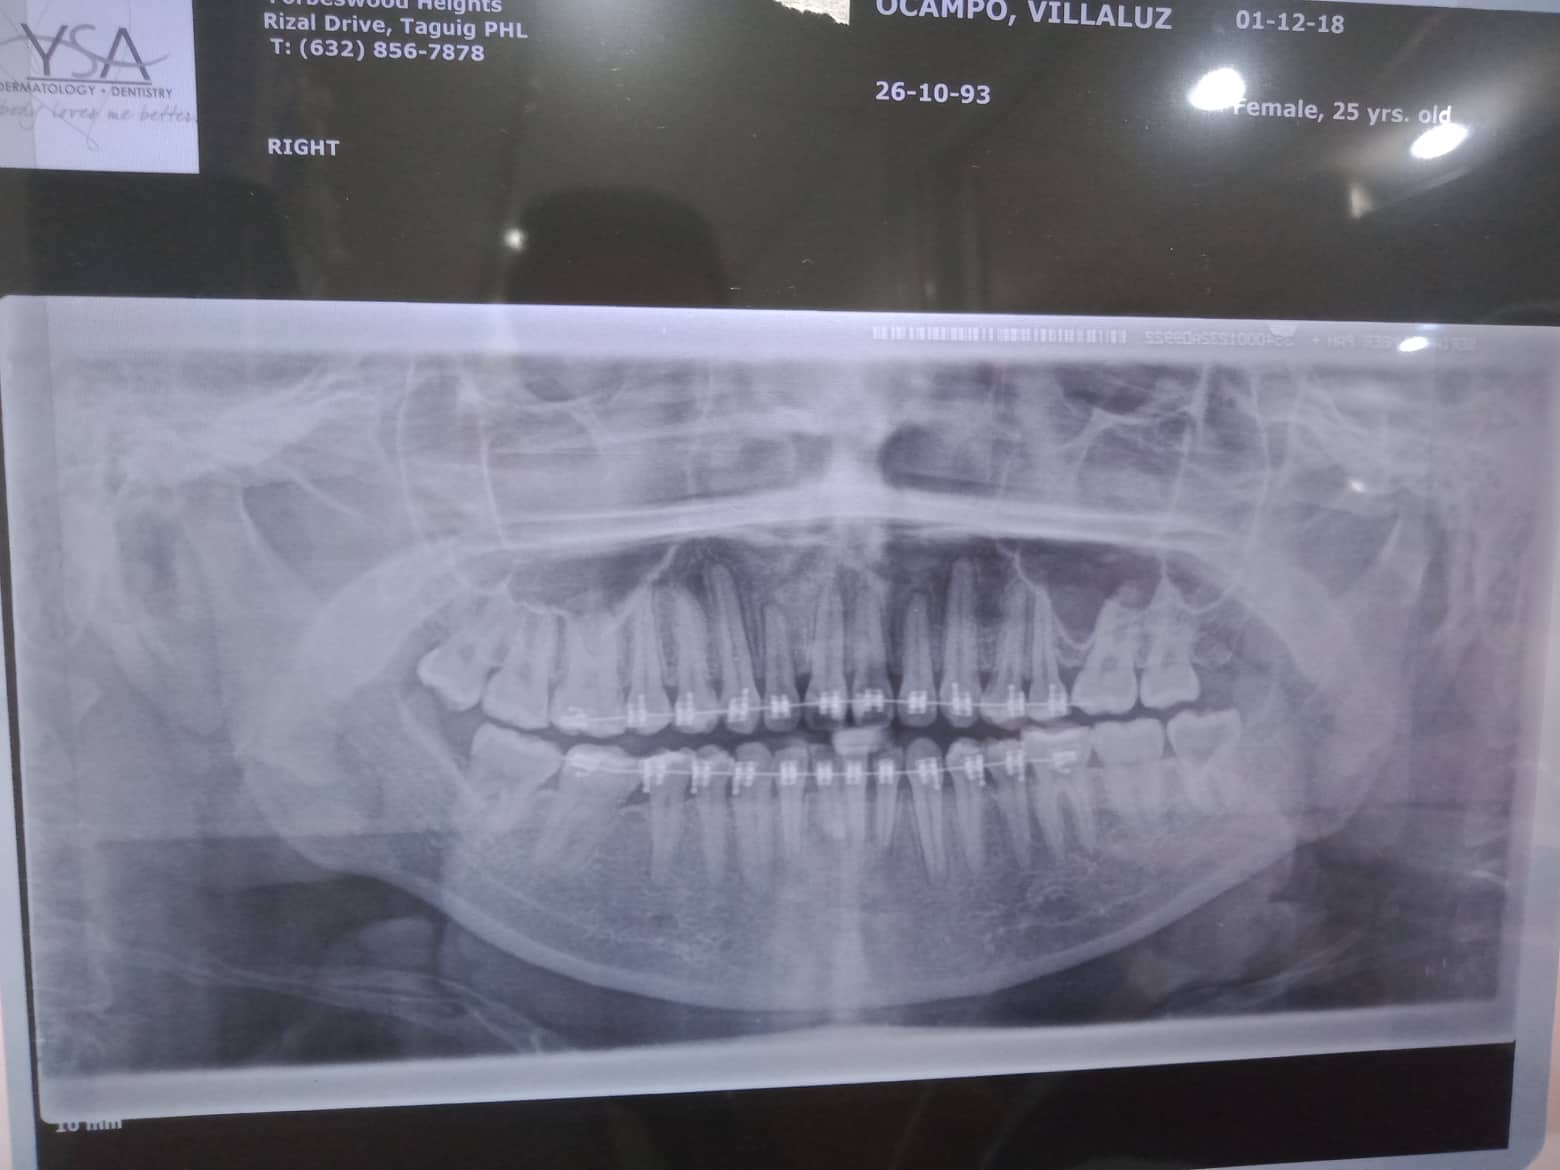

Patient Info

- Last Name

- Canonero

- First Name

- Villaluz

- Middle Name

- Ocampo

- Birthdate

- October 26, 1993

- Procedure

- 03/16/24 LC #17-OCC+lingual deep carries #18-OCC + lingual ozone OP 03/23/24 Lc # 37 OB (deep cavity) #38 OB 04/13/24 LC #11 facial,mesial,distal #21 mesial,distal,facial 11/14/25 OP - mild PA xray LC #16 Occ & lingual #47 Occ